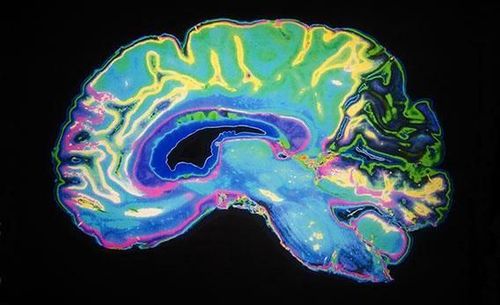

तर आणखी थोडा अभ्यास केला असता असे दिसून येते की, चुंबन हा हार्मोन्सचा खेळ आहे. आपण जेव्हा चुंबन घेतो तेव्हा मेंदूमध्ये ‘ऑक्सिटोसीन’ नावाचे हार्मोन पाझरते. या हार्मोनला ‘लव्ह हार्मोन’ असे सुद्धा म्हटले जाते. ऑक्सिटोसीन आपल्या मेंदूत आनंदलहरी निर्माण करते आणि याच हार्मोनमुळे घनिष्ठता वाढते.

2013 मध्ये केल्या गेलेल्या अभ्यासानुसार ऑक्सिटोसीन नात्यांमधील बंध मजबूत करण्यासाठी आणि जोडीदाराविषयी एकनिष्ठता राखण्यासाठी अत्यंत महत्वाची भूमिका निभावते.

महिला जेव्हा आपल्या बाळाला छातीशी धरून दूध पाजवतात तेव्हा हेच हार्मोन स्रवते. त्यामुळे आई आणि मुलांमधील वात्सल्य आणि प्रेमाचे नाते आणखी घट्ट होते.

तर मंडळी ही कलिजा खलास करण्याची करामत ‘डोपामाईन’ या हार्मोनची आहे बरं का! डोपामाईन हार्मोन हे एखाद्या प्रिय व्यक्तीच्या सहवासात असताना वेगाने स्रवते. याला हॅपी हार्मोन असेही म्हणतात. हे जेवढे जास्त स्त्रवेल तेवढेच शरीराला आणखी हवे असते. थोडक्यात याचे व्यसनच लागते म्हणा ना. ‘लीप लॉक’ अवस्थेत असताना याचे प्रमाणही सर्वोच्च पातळीवर पोचलेले असते. म्हणूनच ओठ लवकर विलग करावे वाटत नाहीत. आहे की नाही गंमत?